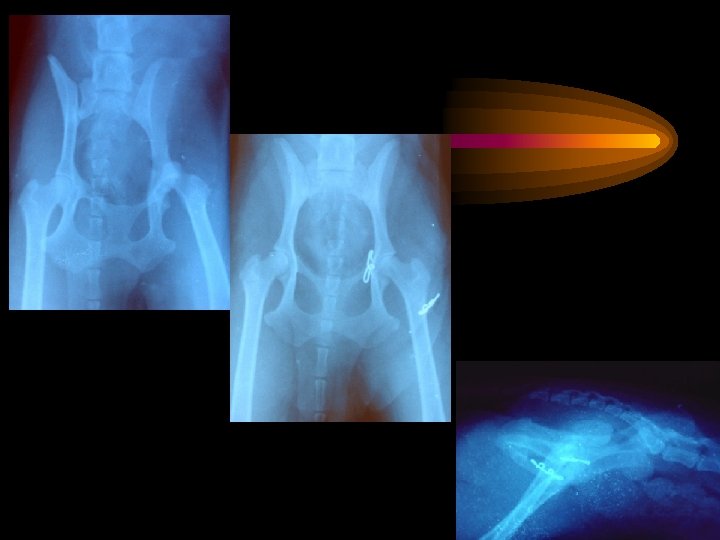

Tanım • Coxo-femoral luksasyon, kalça eklemini oluşturan kaput femoris’in acetabulumdan ayrılarak değişik derece ve yönlerde yer değiştirmesidir. Kalça eklemi luksasyonları kalça çevresindeki yumuşak dokuların ve artiküler kıkırdağın dejenerasyonunun önlenmesi amacıyla mümkün olan en kısa sürede yapılmalıdır.

Tanı • Bacağın hareketleri krepitasyon ve ağrıya neden olur. • Normal tarafla karşılaştırılınca trochanter major ve tuber ischii arasında asimetri belirgindir. • Kalça eklemi luksasyonu ventrodorsal ve lateral radyografilerle kesinleştirilir

Operatif tedavi • Kapalı redüksiyonda başarılı olunamamışsa, interpozisyon ve kas spazmları gelişmişse • Fovea kapitiste bir avülsiyon kırığı, collum femoris, trochanter major ve acetabulum kırıkları söz konusu ise, açık redüksiyon endikedir. • Kalça ekleminin stabilizasyonuna çok sayıda rekonstrüksiyon tekniği ile ulaşılabilir. • Kalça displazisi ise, asetabulumun gelişimindeki yetersizlik ve ikincil olarak gelişen femur başı lezyonları ile özel bir durum oluşturur. • Eğer eklem yapısından önemli değişiklikler oluşmuş ise, eksizyon artroplasti ve total kalça protezi gibi alternatif yöntemler düşünülmelidir.

Operatif Tedavi Yontemlerinin bazıları • De Vita Pin Uygulaması • Eklem kapsülünün onarımı • Prostetik kapsül rekonstrüksiyonu Trochanter majorun yeniden yönlendirilmesi • Transartiküler pin uygulaması • Tek dikiş uygulaması • Knowles Toggle Pin Uygulaması • Elastik eksternal fiksatör uygulanması